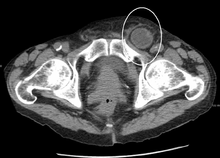

In the diagnosis of abdominal hernias, imaging is the principal means of detecting internal diaphragmatic and other nonpalpable or unsuspected hernias. Multidetector CT (MDCT) can show with precision the anatomic site of the hernia sac, the contents of the sac, and any complications. MDCT also offers clear detail of the abdominal wall allowing wall hernias to be identified accurately.[8]